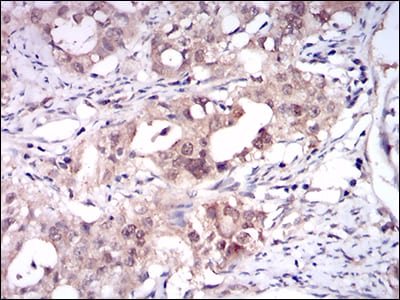

Immunohistochemical analysis of paraffin-embedded human cervical cancer tissues using ONECUT3 mouse mAb with DAB staining.

Immunohistochemical analysis of paraffin-embedded human rectum cancer tissues using ONECUT3 mouse mAb with DAB staining.